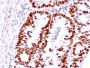

Positive Control

HCT116, MCF-7, A431 or HeLa cells. Colon Carcinoma.

Antibody target cellular localization

Nucleus

IF (verified)|IHC, FFPE (verified)|WB (verified)

IF (verified)|IHC (FFPE) (verified)|WB (verified)